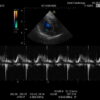

Hitachi EUP-S70 Ref Phased Array – HI VISION

Hitachi Phased Array EUP-S70 Cardio

Intended use

Cardiology and Transcranial

Frequency Range

5 – 1 MHz

Hitachi EUP-S70 Phased Array – HI VISION

Frequency Range: 5 – 1 MHz

Scan Angle: 90° FOV

HI VISION Connector

Hitachi EUP-S70 Phased Array – HI VISION for Cardiology and Transcranial

Compatible with Hitachi Hi Vision systems